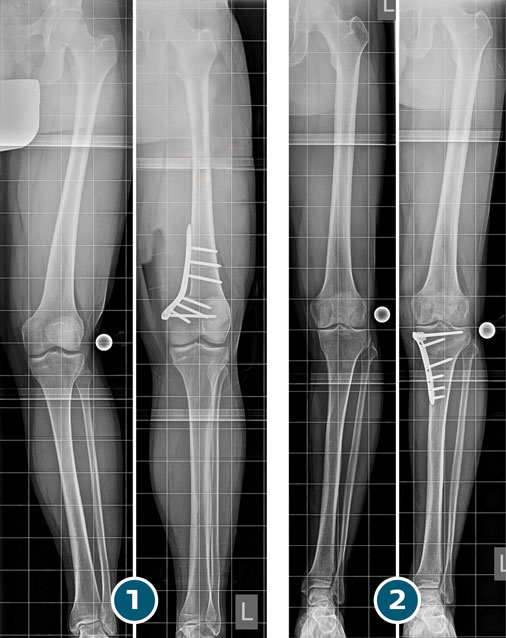

Beinachsenkorrektur durch Umstellungsosteotomie: Röntgenaufnahmen vor und nach der OP bei einem X-Bein (1) und einem O-Bein (2).

- Die Korrektur erfolgt in der Regel durch eine aufklappende oder zuklappende Umstellungsosteotomie.

- In allen Fällen erfolgt die Stabilisierung der Osteotomie mittels einer winkelstabilen Platte und Schrauben.